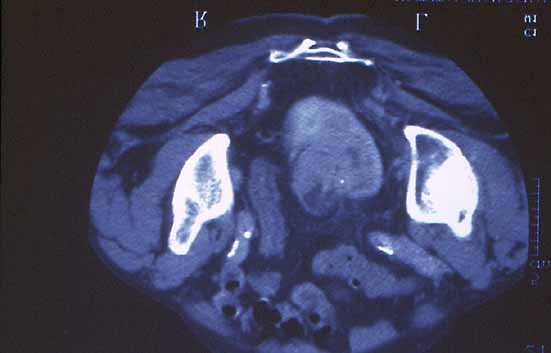

Figura 7.- TAC pélvico:Masa en riñón izquierdo(riñon pélvico)localizada en la pelvis, que infiltra el parénquima y dilata el uréter.